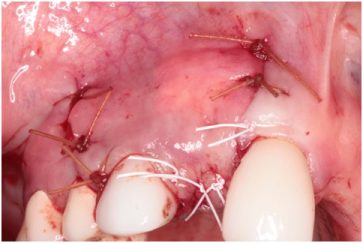

The patient received 2 gm of amoxicillin as an antibiotic prophylaxis (Zimox, Pfizer Inc., USA). Intravenous sedation was administered and approximately 30 cc of venous blood was drawn in order to prepare 3-5 cc of platelet rich fibrin (PRF). 2% Lidocaine HCL 1:100, 000 with epinephrine (Septodont Cook-Waite, Lancaster, PA, USA) was used for local infiltration at the #s 6-11 sites. Both surgical sites were prepared in the same manner. Bilateral papilla sparing incisions were completed (Figure 4 and Figure 5). Once the labial or buccal aspects were exposed, a #7011 bur was used to perforate the bone and establish bleeding bone (Figure 6 and Figure 7). At both sites, a Cytoplast® Ti-250 (Osteogenics Biomedical, Lubbock, TX, USA) titanium reinforced membrane shaped and sized to cover the proposed GBR sites and allow space for the bone regeneration to occur. The membrane each were secured with bone tacks first at the vestibule (Tru Tack® ACE Boston, MA, USA) (Figure 8). Then MinerOss® bone graft (Biohorizons, Birmingham, AL, USA) was placed at both surgical sites (Figures 9 and Figure 10) followed by a single superior membrane bone tack (Figures 11 and Figure 12). PRF was placed over the membranes (Figures 13 and Figure 14) and the surgical flaps were repositioned without tension with Cytoplast® and chromic sutures (Figures 15 and Figure 16).

Figure 15: Flap repositioned without tension using Cytoplast® and chromic sutures at the #7 site. View Figure 15

Figure 16: Flap repositioned without tension using Cytoplast® and chromic sutures at the #s 9 and 10 sites. View Figure 16